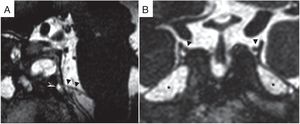

Se ha documentado el aumento bilateral y simétrico de los espacios de LCR alrededor de los nervios del III par en la pared lateral del espacio lateroselar o en la entrada del canal de Dorello del VI par (fig. 7)27. Son necesarios más estudios que evalúen su valor diagnóstico real.

Aumento de los espacios de líquido cefalorraquídeo (LCR). A) Secuencia balanceada fast imaging employing steady-state (FIESTA) en el plano sagital de un paciente con HII. Se demuestra el relleno por LCR del canal dural del VI par (canal de Dorello) (punta de flecha blanca y negra). B) Imagen coronal de secuencia FIESTA con un aumento bilateral y simétrico de los espacios de LCR (asteriscos) alrededor de los canales durales del III par (puntas de flecha negra) en la pared lateral del espacio lateroselar. Se identifican también meningocele del cavum de Meckel (asteriscos) asociados a la HII.